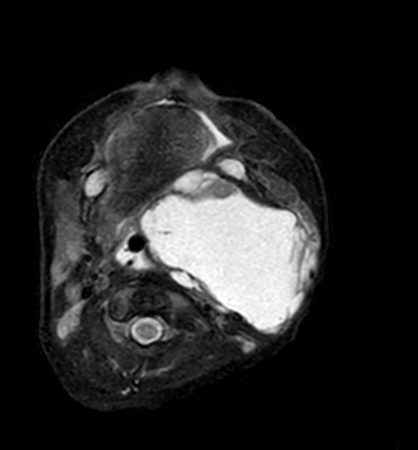

Axial mDIXON XD - T1w TSE (Water only)

Axial mDIXON XD - T1w TSE (In Phase)